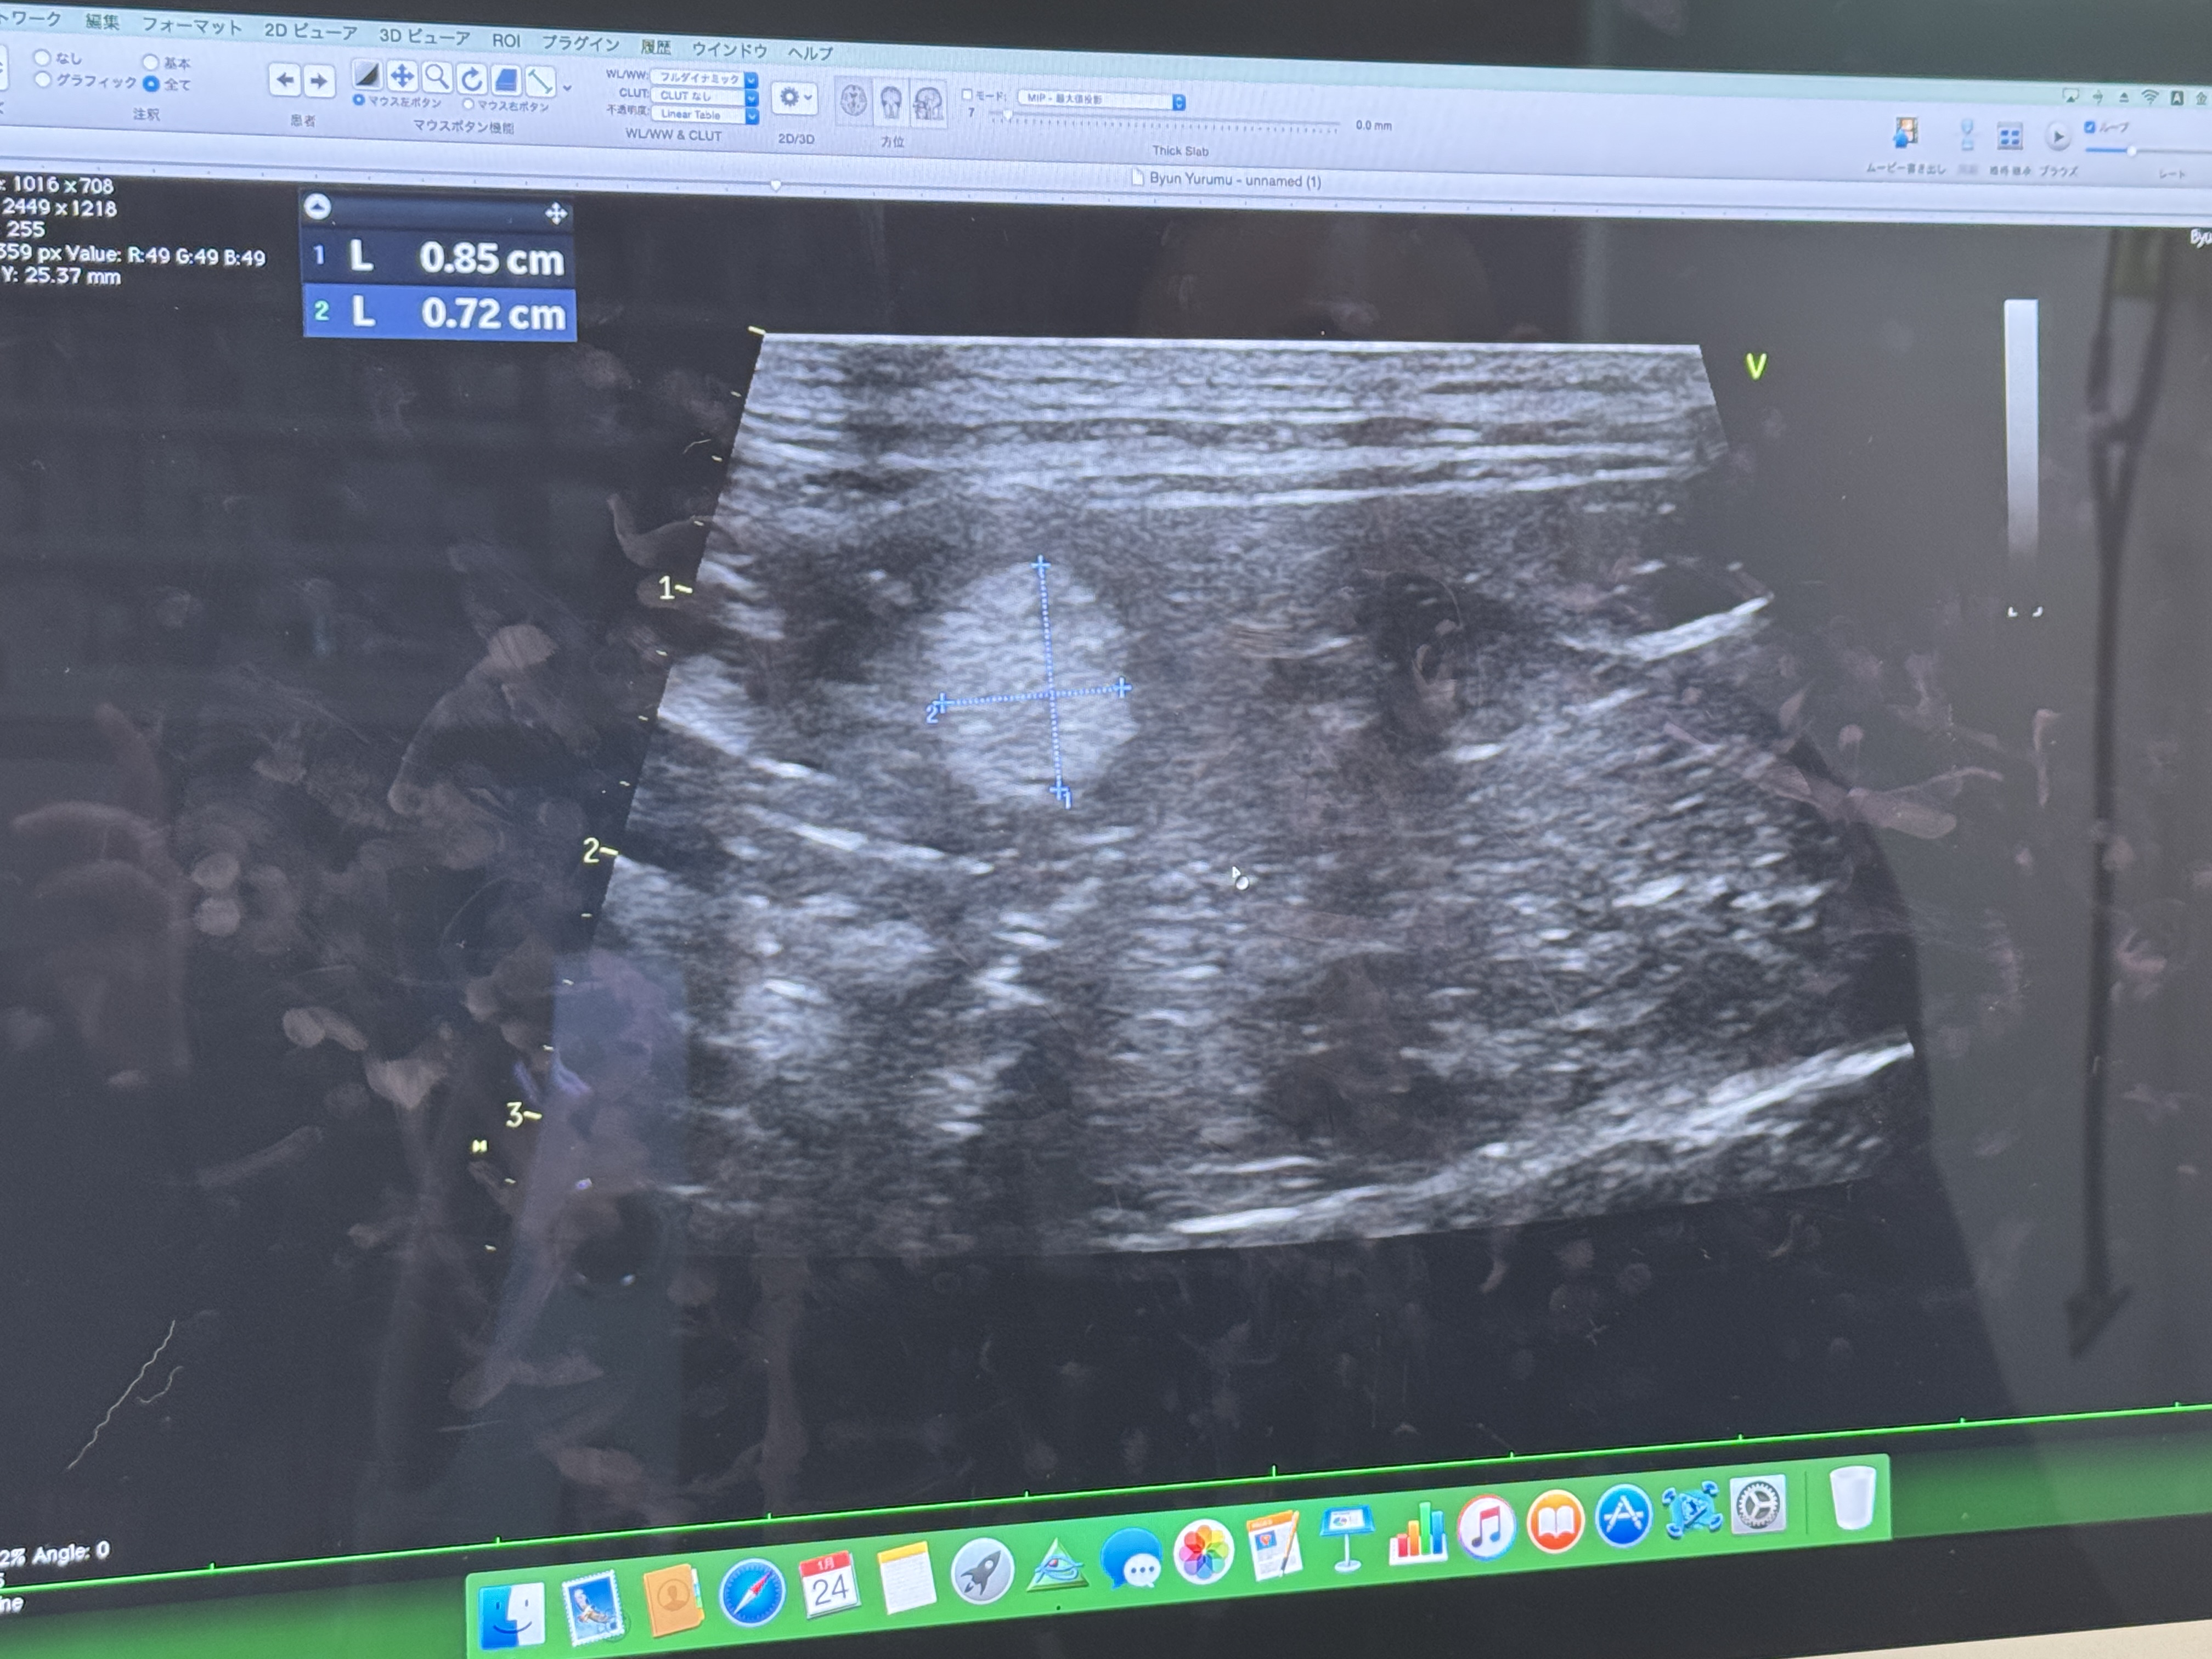

얼마전에 다녀온 율무 건강진단.

비장 종양의 증상으로는 복부 팽만, 식욕 부진, 무기력, 구토 등이 있으며, 심한 경우 비장 파열로 인한 급성 쇼크나 사망을 초래할 수 있습니다. 초음파 검사를 통해 종양을 발견하고, CT 검사와 조직검사를 통해 정확한 진단을 내립니다.